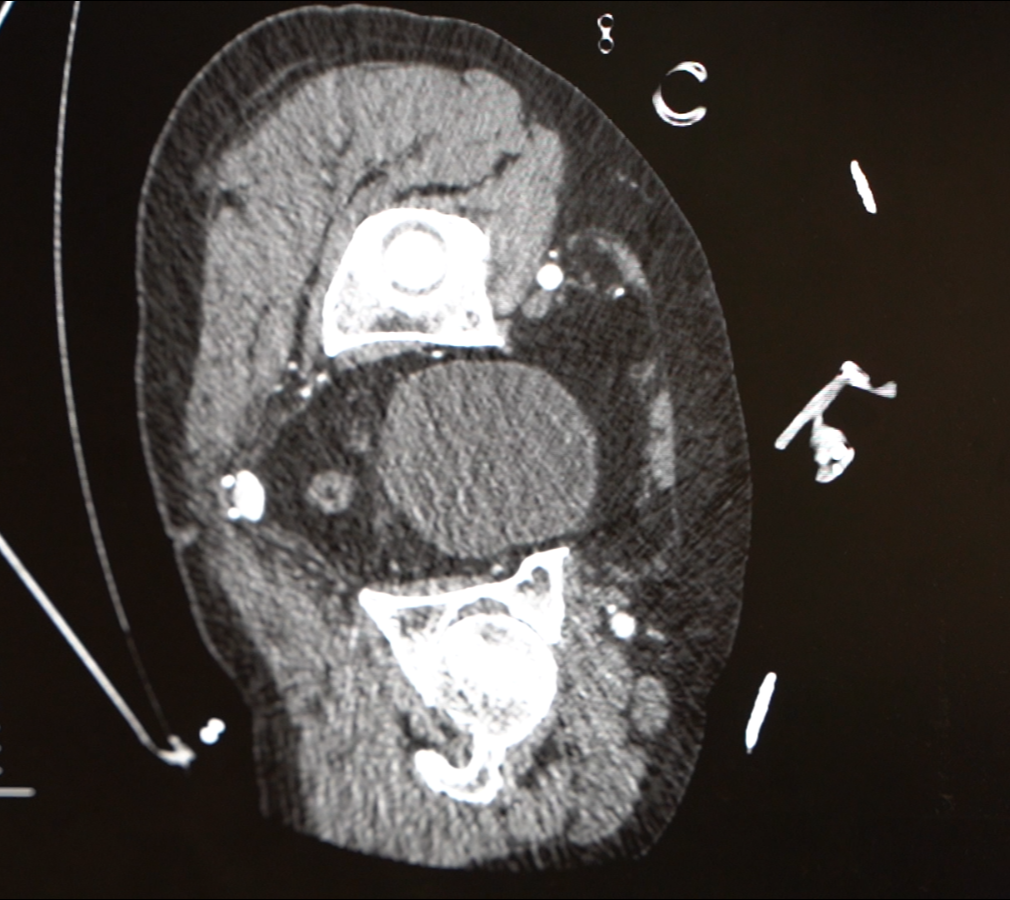

急诊检查结果不容乐观:胸腹主动脉夹层伴胸腔大量积液、纵隔积液——这些积液,考虑是从撕裂的主动脉里漏出来的!

医院心脏血管外科团队紧急会诊,这虽是B型主动脉夹层,但极其凶险,而且他已出现休克表现。“主动脉夹层就像水管壁分层开裂,一旦完全破裂,血液会瞬间涌入胸腔,没有任何抢救机会。他这种情况,已经是命悬一线。”心脏病院副院长张金洲语气凝重。

好在经过医务人员63分钟的紧急抢救,章先生终于脱离了生命危险。可是危机并未完全解除。术后的章师傅心率快,血压持续偏低,转入心外ICU,主管医生时乐祥发现,他的心脏因失血过多几乎呈“空泵”状态。